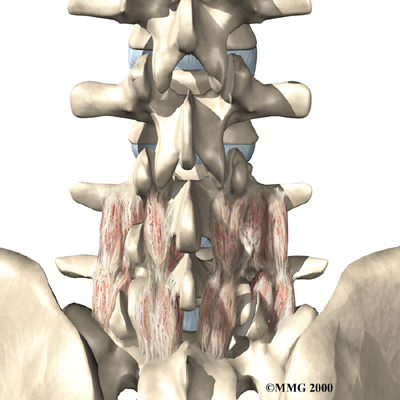

The human spine is formed by 24 spinal bones, called vertebrae. Vertebrae are stacked on top of one another to form the spinal column. The spinal column gives the body its form. It is the body's main upright support. The section of the spine in the lower back is known as the lumbar spine.

The lumbar spine is made up of the lower five vertebrae. Doctors often refer to these vertebrae as L1 to L5. These five vertebrae line up to give the low back a slight inward curve. The lowest vertebra of the lumbar spine, L5, connects to the top of the sacrum, a triangular bone at the base of the spine that fits between the two pelvic bones. Some people have an extra, or sixth, lumbar vertebra. This condition doesn't usually cause any particular problems.

Intervertebral discs separate the vertebrae. The discs are made of connective tissue. Connective tissue is the material that holds the living cells of the body together. Most connective tissue is made of fibers of a material called collagen. These fibers help the disc withstand tension and pressure.

A disc is made of two parts. The center, called the nucleus, is spongy. It provides most of the disc's ability to absorb shock. The nucleus is held in place by the annulus, a series of strong ligament rings surrounding it. Ligaments are connective tissues that attach bones to other bones.